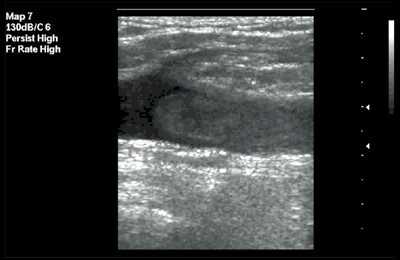

При аномалии расположения отмечалось обратное расположение сосудов: внутренняя яремная вена находилась более глубоко и медиально по отношению к сонной артерии. Как правило, диаметр внутренней яремной вены при аномалии расположения сосудов был существенно меньше диаметра сонной артерии (рис. 5). Все аномалии имели односторонний характер.

Рис. 5. Аномалия расположения и размера внутренней яремной вены (вена располагается медиальнее артерии, ее размер существенно меньше размера артерии).